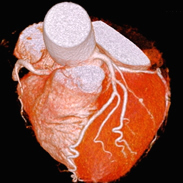

X線CT検査

X線装置を回転させることで、体内の断面像を画像として得ることができます。

造影剤という薬品を用いることで、血管や病変部を強調することもできます。

また、画像処理することにより、立体的な表示や血管部分のみを描出することもできます。

「診断部門」に320列CT装置と64列CT装置、救急外来に80列CT装置が稼働しています。

320列エリアディテクタCT装置のご紹介

この装置は、センサーが1回転する間に16cmの幅を撮影することができ、頭部や心臓などこれまでになく精確なスキャンを行うことができます。

- ・心臓領域

- 安定狭心症、急性冠症候群、経皮的冠動脈形成術・冠動脈パイパスの術後評価などに有用です。

64列CT装置に比べて息を止める時間が短くてすみ、患者様の負担が大幅に軽減されます。また、従来はよい画像を得ることが難しかった不整脈のある方についても、明瞭に描出する能力があります。 - ・体幹部領域